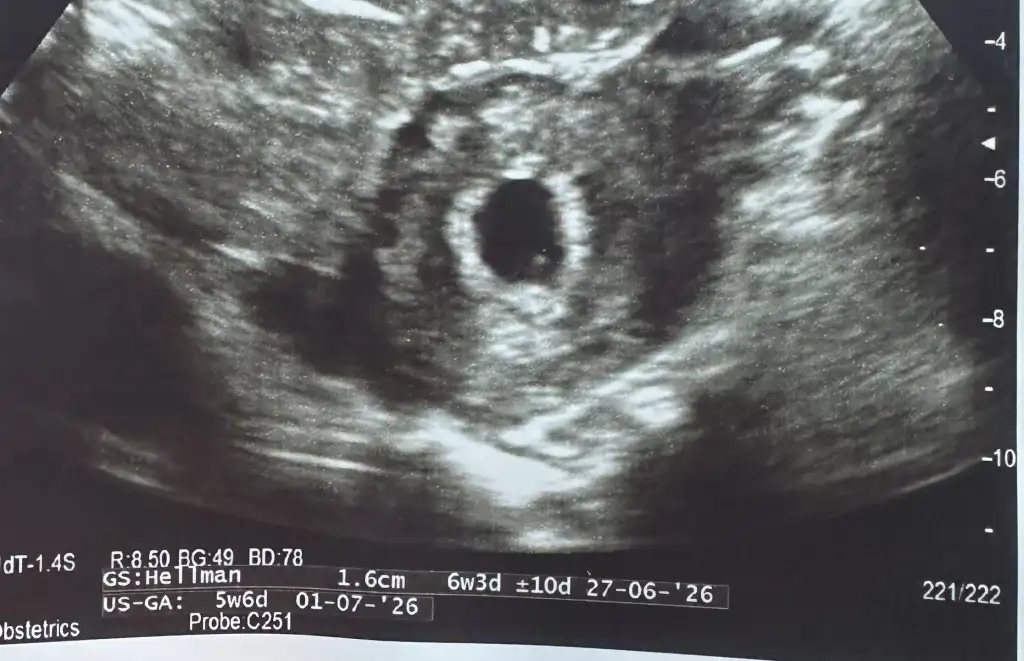

Kızlar merhaba çok şükür bugün biz de keseyi gördük 5 + 5’te karından gördük yolk sacıda gördük sağlıklı bir gebelik gibi görünüyor dedi haftaya kalp atışı için gidicez inşallah bebeğin kalbi atmaya başladıktan sonra mide bulantısı başlar dedi genelde yani altıncı haftadan önce midem bulanmıyor diye endişeden anneler korkmasın

Şu görüntü beni duygulandırıyor ya inşallah duyarsın canımmm sağlıkla büyüsün